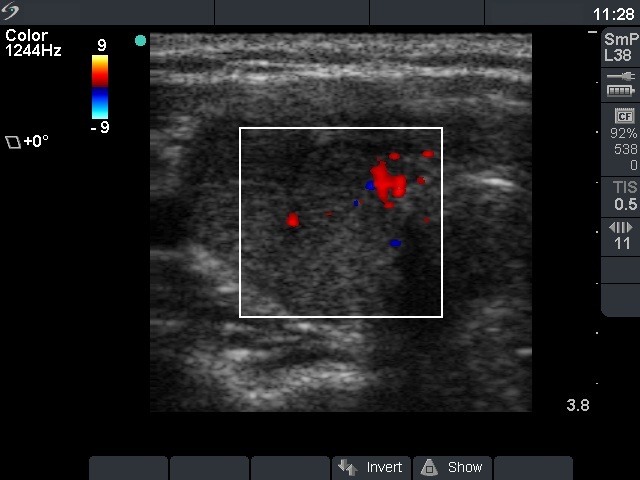

First examination (first and second row of images):

Clinical presentation: A 33-year-old woman was referred with typical complaints of subacute thyroiditis lasting for 6 weeks.

Palpation: Both lobes were hard and painful.

Functional state: moderate degree of hyperthyroidism with TSH-level 0.001 mIU/L, FT4 27.2 pM/L. Erythrocyte sedimentation rate was 49 mm/H, CRP was 9.2 mg/L.

Ultrasonography: The thyroid was hypoechogenic and inhomogeneous. The vascularization was average.

Cytological diagnosis: subacute, granulomatous de Quervain's thyroiditis.

Suggestion: steroid therapy for 6 weeks.